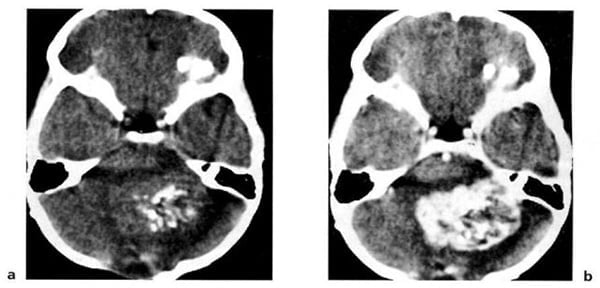

Hình 1.59. U màng ống nội tủy. Trước tiêm (a), không đồng nhất nằm ở vùng não thất 4 (mũi tên). Sau tiêm (b), bắt chất cản quang mạnh và không đồng nhất.

Hình 1.66. Di căn từ ung thư tế bào đáy đến bán cầu tiểu não bên phải. U bị hoại tử và bắt chất cản quang dạng viền.